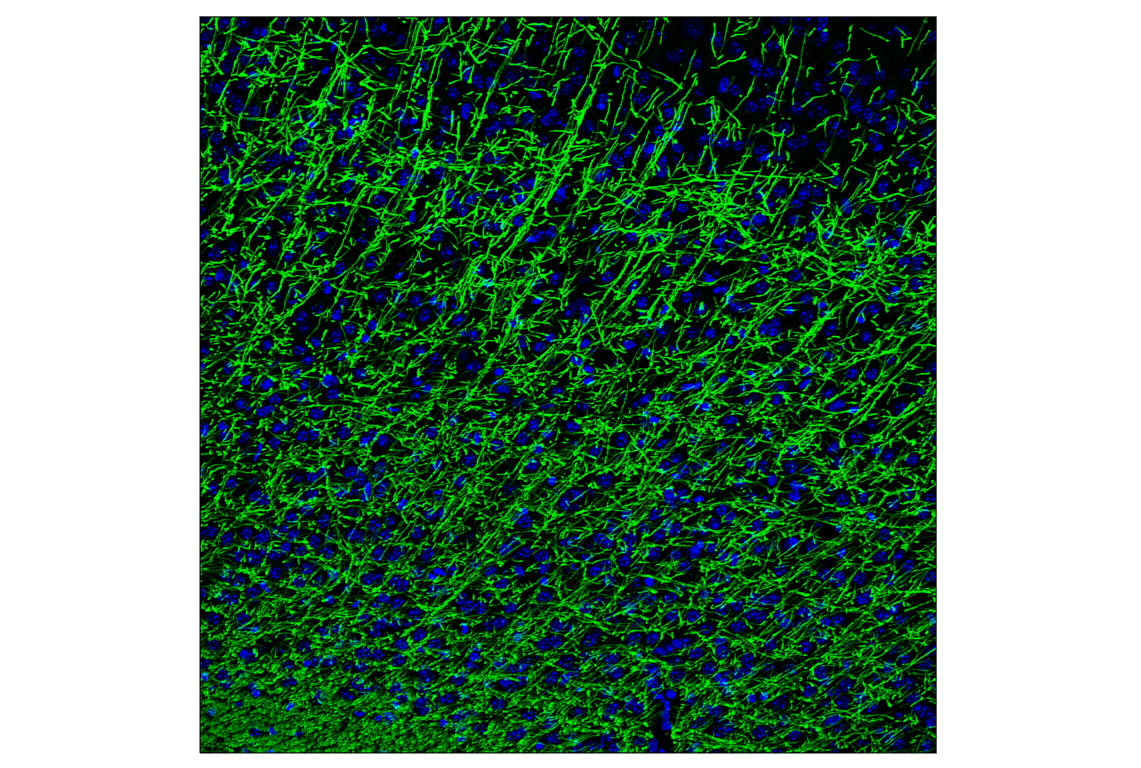

Myelin Basic Protein (D8X4Q) Mouse Chimeric Monoclonal Antibody #38521

Immunofluorescence (Frozen) 1:50 - 1:200

Myelin Basic Protein (D8X4Q) Mouse Chimeric Monoclonal Antibody recognizes endogenous levels of total myelin basic protein.

Myelin basic protein (MBP) is an abundant central nervous system (CNS) myelin membrane protein that plays an important role in nerve myelination. Myelin sheaths are multi-layered membranes derived from oligodendrocytes that increase the conduction velocity of axonal impulses. MBP helps to adhere the cytoplasmic leaflets of adjacent oligodendrocyte membranes to one another. Several splice variants of MBP are expressed in cells and the protein is modified following translation (i.e., phosphorylation, methylation), which suggests additional membrane adhesion functions (1).